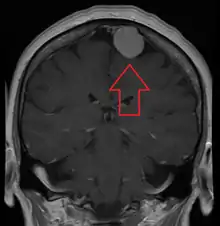

A meningioma that previously had been operated on, with surrounding edema

MRI image of a meningioma with contrast

Meningiomas are visualized readily with contrast CT, MRI with gadolinium,[22] and arteriography, all attributed to the fact that meningiomas are extra-axial and vascularized. CSF protein levels are usually found to be elevated when lumbar puncture is used to obtain spinal fluid. On T1-weighted contrast-enhanced MRI, they may show a typical dural tail sign absent in some rare forms of meningiomas.[17]